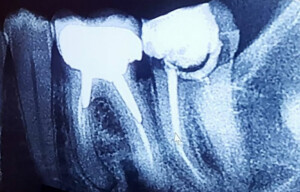

La radiographie 2D numérique de contrôle

À la fin de l’opération d’endodontie, une radiographie de contrôle est effectuée. Celle-ci a pour but de confirmer le succès du protocole ; elle vérifie que le traitement a obturé l’intégralité de la longueur des racines de la dent dévitalisée. Les appareils de radiologie modernes sont désormais sur le mode numérique et considérablement moins ionisants que les modèles argentiques anciens.

La pose de couronne